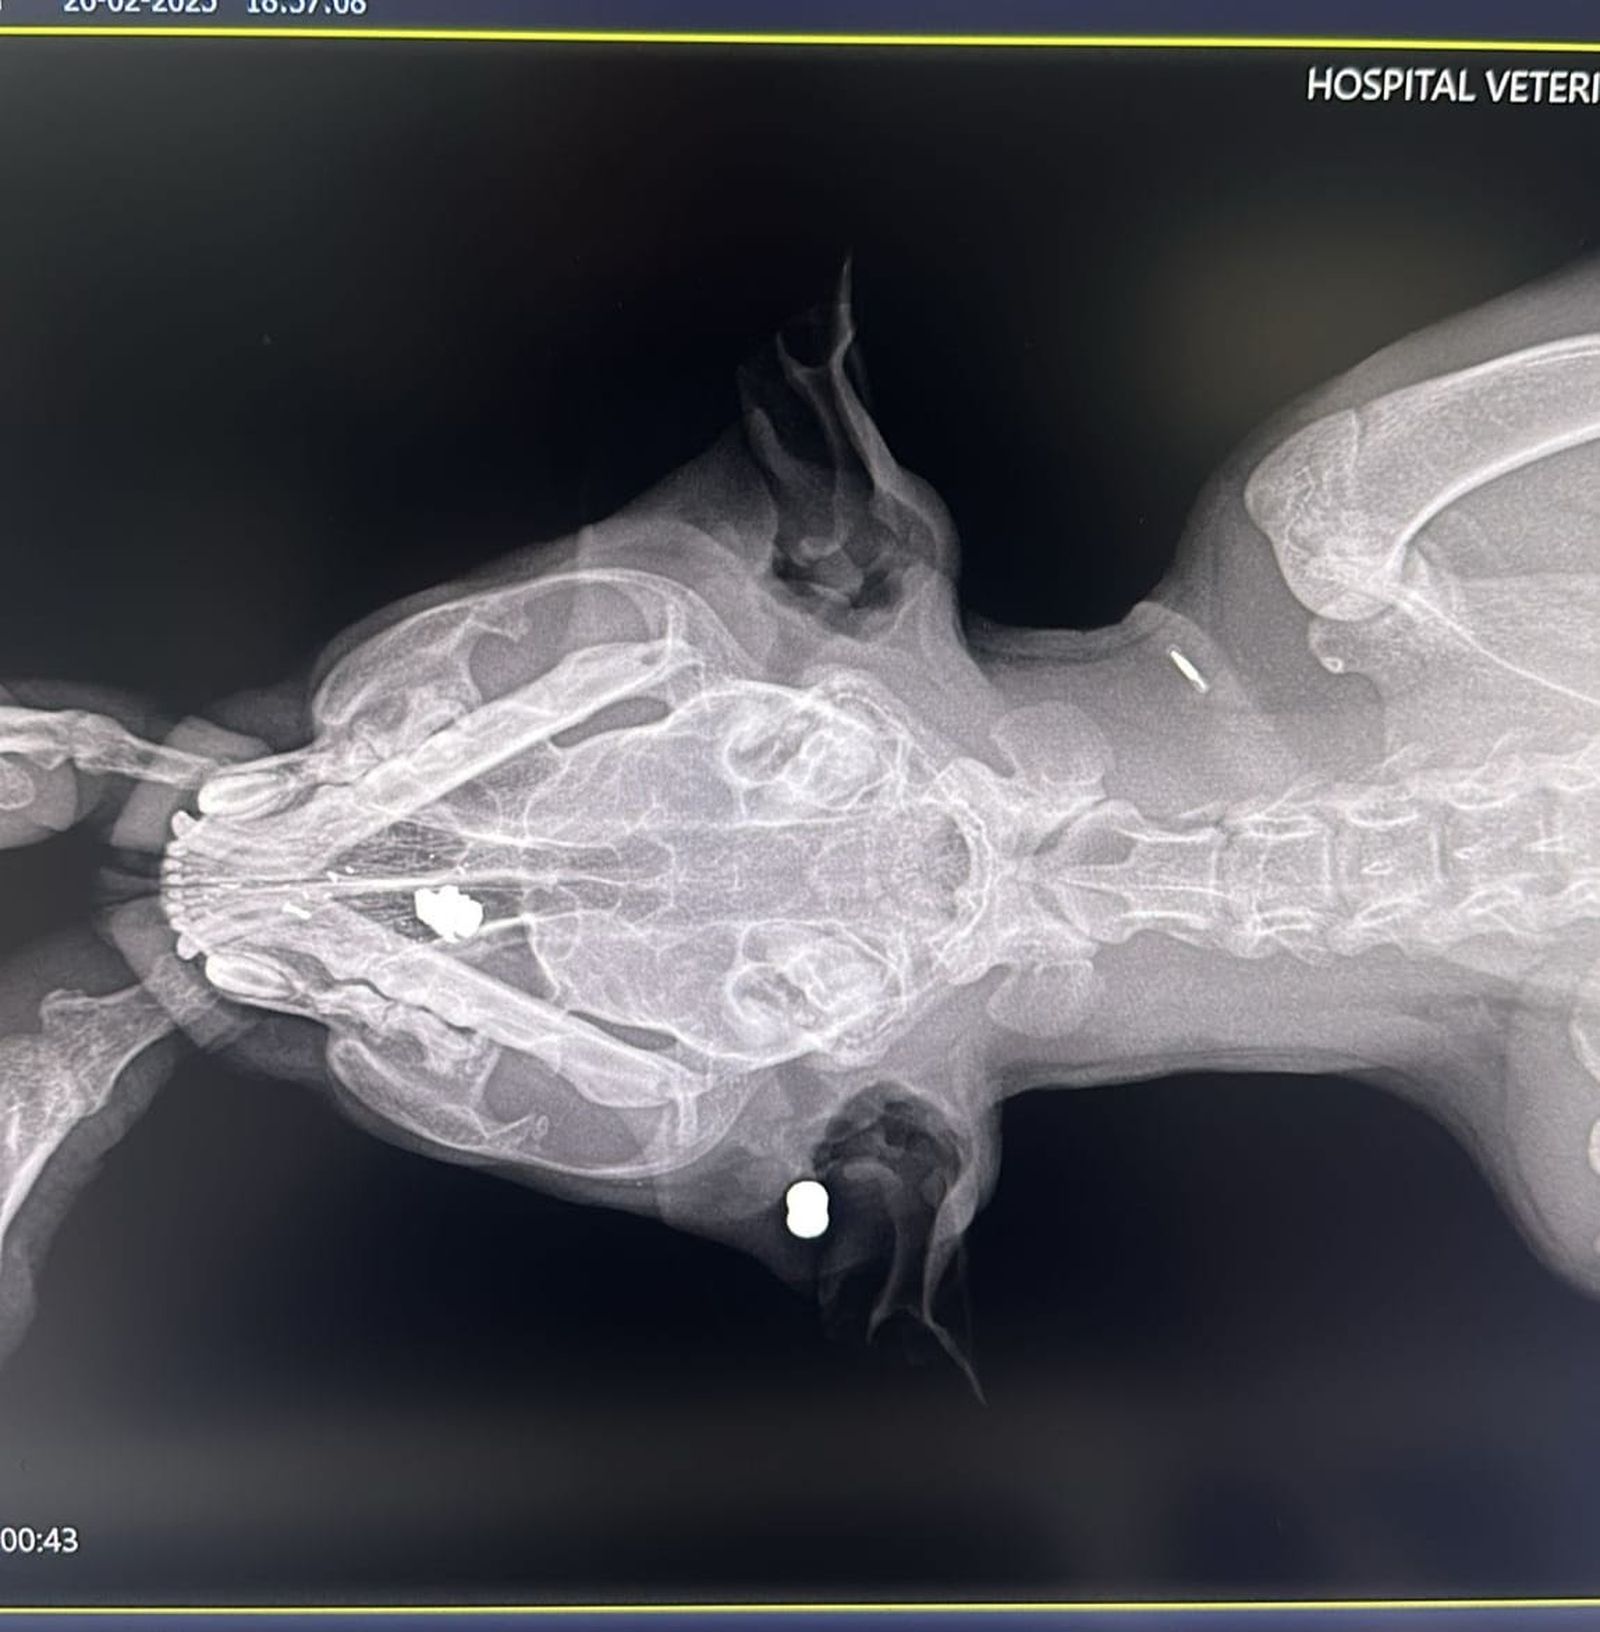

Radiografía que refleja los disparos sufridos por el animal.

Radiografía que refleja los disparos sufridos por el animal. / EQUINAC

Según ha informado Eduardo Milla, coordinador de PACMA en la provincia de Almería, la colonia afectada está controlada por cuidadoras que han implementado el método CER (Captura, Esterilización y Retorno), asegurando que los gatos están identificados, esterilizados y desparasitados. No obstante, cuando se disponían a iniciar el proceso de esterilización de los machos, detectaron que uno de los gatos presentaba un grave deterioro de salud, y tras una revisión veterinaria, se confirmó que tenía varios perdigones en su cuerpo que ponían en peligro su vida.